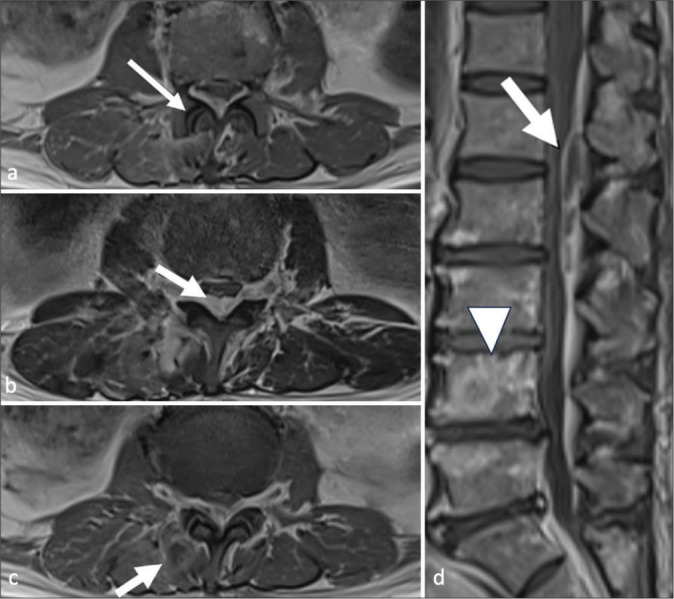

面关节化脓性关节炎是一种罕见的严重脊柱感染,但由于其临床表现和影像学表现不特异,常常被误诊。本系列病例展示了面关节化脓性关节炎患者的各种临床表现、影像学特征和预后。我们展示了不同的疾病分期,以帮助临床医生和放射科医生识别这种疾病。同时还讨论了关键的诊断误区,以提高临床实践中诊断的准确性。

Facet joint septic arthritis is a rare; yet, severe spinal infection often misdiagnosed due to its non-specific clinical presentation and radiological mimickers. This case series illustrates various clinical presentations, imaging features, and outcomes of patients with facet joint septic arthritis. We demonstrate different disease stages to aid clinicians and radiologists in recognizing this condition. Key diagnostic pitfalls are also discussed to enhance diagnostic accuracy in clinical practice.